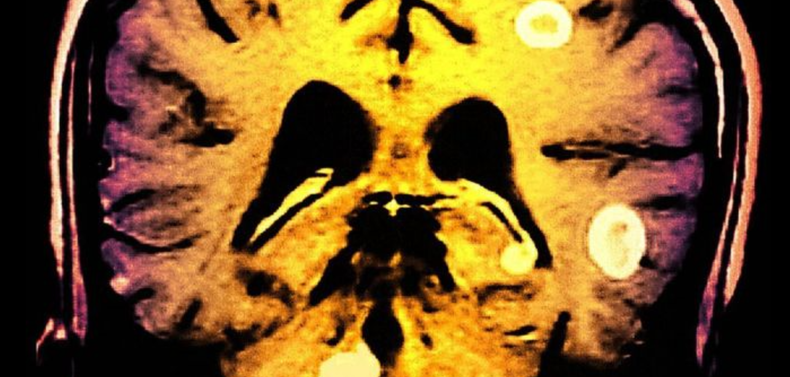

Tuberculosis en el cerebro: "El dolor es tan fuerte que me dan ganas de cortarme la cabeza"

Johnny Islam, 29, es de Leyton, un barrio de Londres. Aunque sufrir de tuberculosis en el cerebro es inusual, la enfermedad en sí es más común de lo que se piensa.

La enfermedad le cambió la vida a Johnny. Podría causarle daño permanente y hasta matarlo.

"Se puede propagar a todas las células cerebrales, puede perjudicar tu memoria. A mí se me olvidan cosas todo el tiempo".